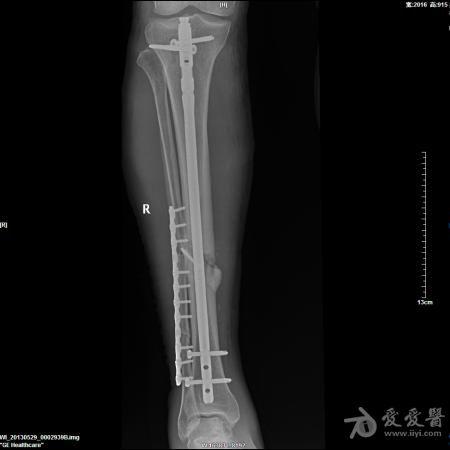

胫骨开放性骨折髓内针固定

57岁男性,骑摩托车摔伤,诊断1.右胫骨开放粉碎性骨折 2.腓骨粉碎性骨折 3.左锁骨粉碎性骨折(近、远端) 4.左肩胛骨粉碎性骨折 5.颅脑外伤。

入院后急诊清创缝合、右跟骨牵引,第9天,颅脑外伤稳定后行手术治疗。

这是术后片,术前片随后奉上。

胫骨髓内固定很好,远端的锁钉看不到了,不明白。至于胫骨的骨块上的螺钉和腓骨的板子,个人愚见纯属多余。

腓骨中断骨折没必要固定,而且固定不是很好。胫骨骨折断端的螺钉画蛇添足,影响愈合

楼主的手术观点可行,只是手术技巧还需进一步提高。1肩部的骨折应是一个浮肩损伤,片上隐约可以看到肩胛颈部的骨折,需要进行悬吊复合体完整性的恢复,或许肩胛骨进行固定效果会更理想。2腓骨骨折涉及到胫腓联合上8CM以内,所以需要固定,但胫腓骨的固定顺序错误,应先固定腓骨。如果术前或术中可以证实胫腓间韧带完整,腓骨的近端骨折可以不固定。3,aap髓钉提供立体的远端锁定,可以选择前后向先置钉。4像这样的带楔形骨块的简单骨折,易造成成骨不良,我更愿意选择双骨双钢板固定。